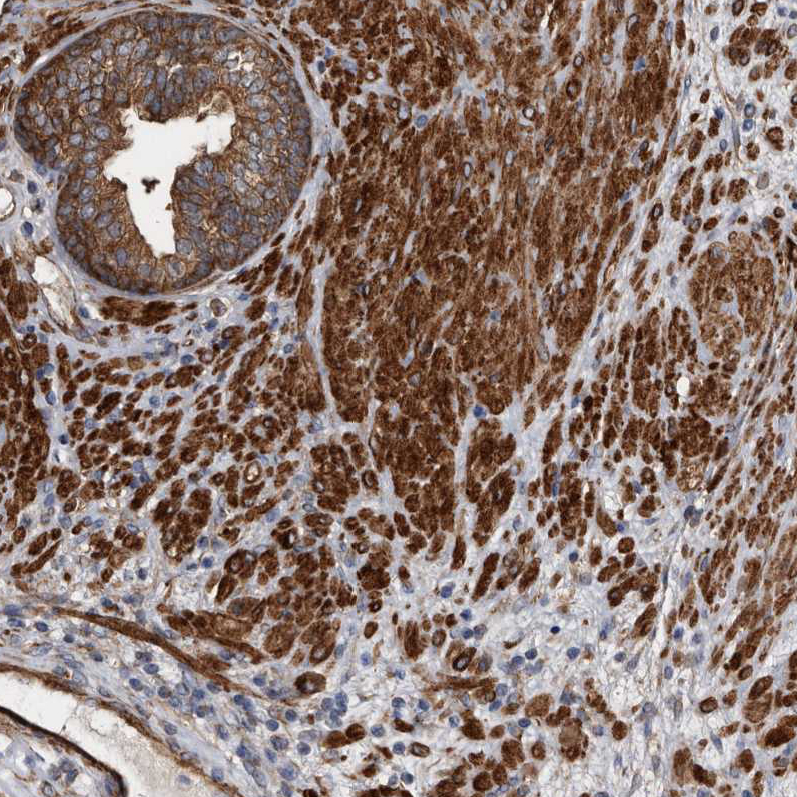

Immunohistochemical staining of human prostate shows strong cytoplasmic positivity in smooth muscle cells.